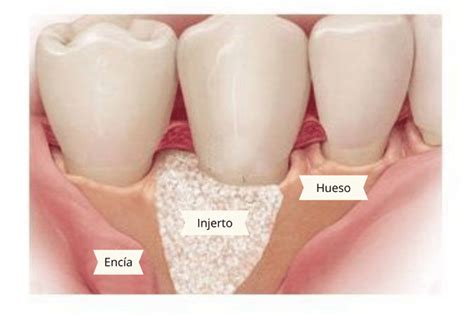

La Solución: Reconstrucción Maxilar con Injertos Óseos

Con las técnicas de reconstrucción de los maxilares mediante injertos óseos, los pacientes, antes condenados a llevar dentaduras postizas, pueden disfrutar de implantes dentales. Este avance ha transformado la vida de muchas personas, permitiéndoles recuperar la funcionalidad y estética de su sonrisa.

Representación esquemática de un injerto óseo para aumentar la densidad ósea en el maxilar.